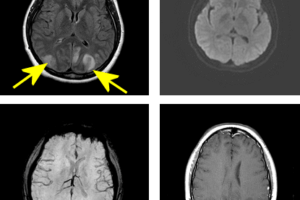

PRES – Posterior Reversible Encephalopathy Syndrome

PRES is an disorder of cerebrovascular autoregulation commonly associated with hypertension  and previosly referred to as eclampsia. Poor sympathetic regulation of the posterior cerebral arteries makes PRES more likely to  involve the... Read more »